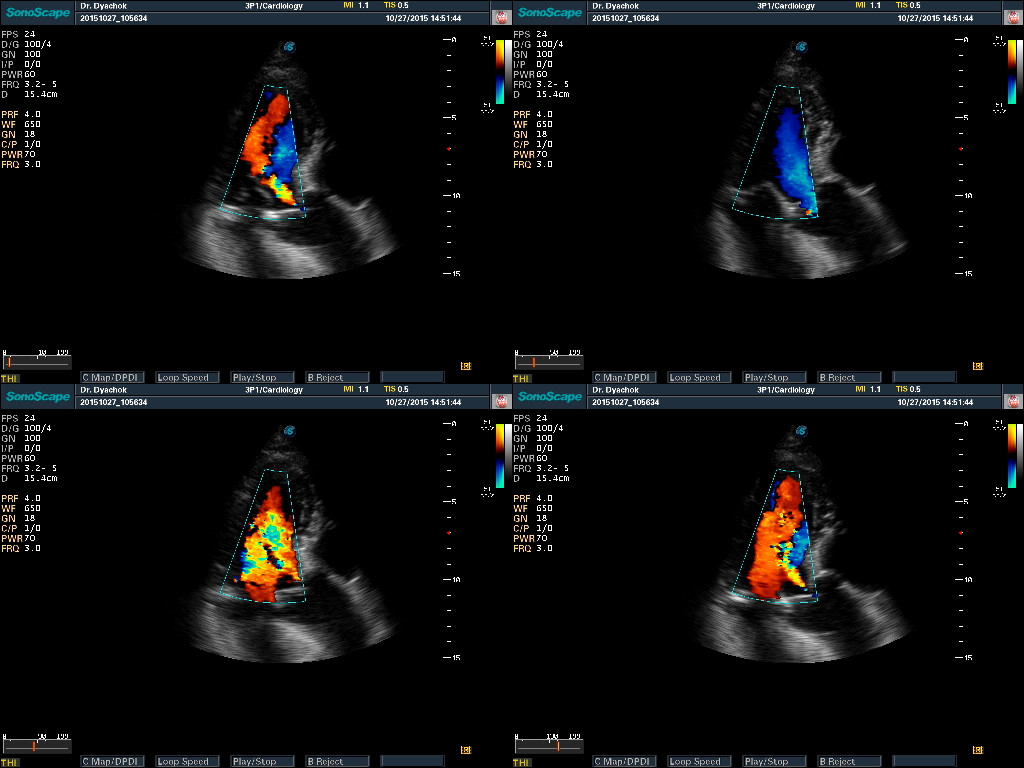

- Весь пакет допплеровских режимов, Strain Rate

- Функция Стресс-Эхо (опция)